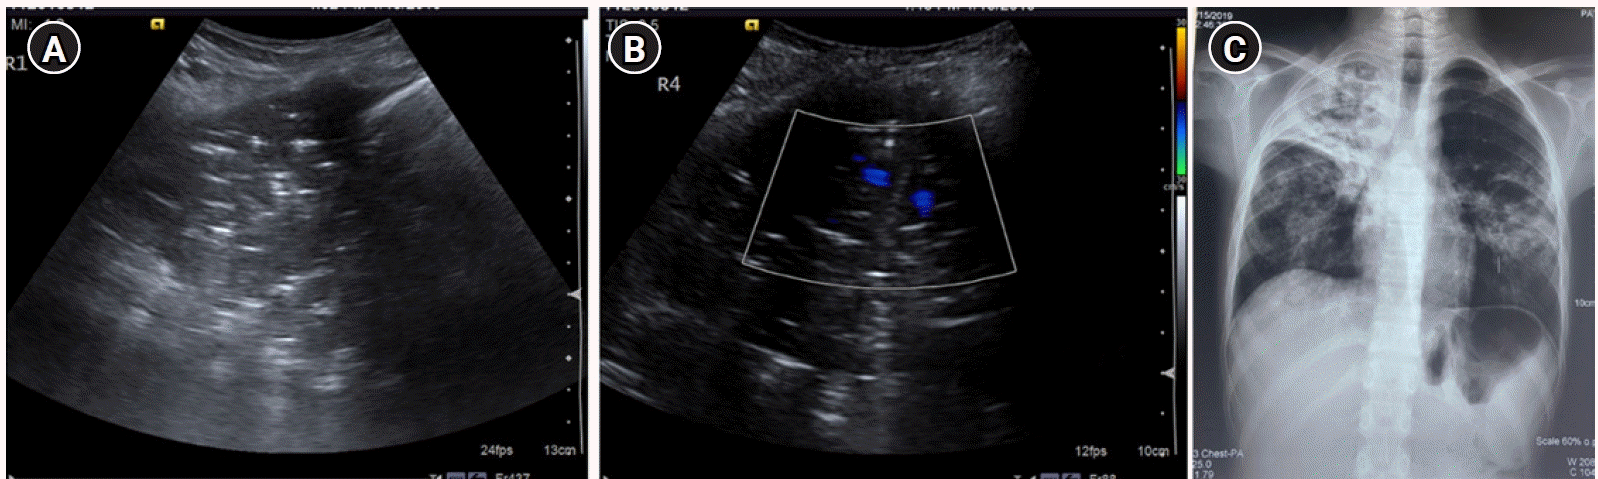

Figure 13.

C profile. (A) Greyscale sagittal ultrasound scan of the right upper anterolateral chest in a 13-year-old female presenting with dyspnea, fever, and cough demonstrating “translobar consolidation” identified by “tissue-like” echotexture, absence of A-lines, presence of sonographic air-bronchograms and a lack of a shredded border. (B) Colour doppler revealed the presence of internal vascularity. (C) Right upper lobe consolidation with air bronchograms was similarly noted on Chest X-ray, correlating with the ultrasound findings.